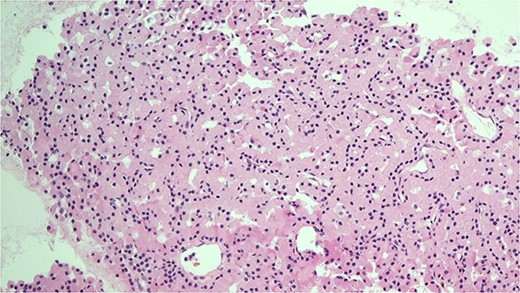

She was subsequently referred to our service for further surgical evaluation. At the time of referral, she was asymptomatic. Initial blood tests showed an elevated PTH of 1256 pg/ml (range 15–65 pg/ml), reduced adjusted calcium of 2.05 mmol/l (range 2.21–2.52 mmol/l), normal free T4 at 19.9 μg/dl (range 12–22 μg/dl), and a reduced TSH <0.01 mU/l (range 0.27–4.20 mU/l), along with a raised phosphate of 2.32 mmol/l (range 0.81–1.45 mmol/l). A CT neck showed a large left thyroid mass with a differential diagnosis of metastatic lymphadenopathy versus a parathyroid adenoma. She underwent an ultrasound and fine needle aspiration of the thyroid mass, which revealed a Thy3A lesion with no evidence of malignancy. Following further multidisciplinary team (MDT) discussion, an immunostain for PTH was performed on the EBUS TBNA, which revealed that the oncocytic cells were positive for PTH (see Figs 1 and 2). This was confirmed by a sestamibi scan, which confirmed a sestamibi-avid nodule (see Fig. 3).

Immunocytochemical stain for PTH which is positive in the cells from EBUS biopsy.